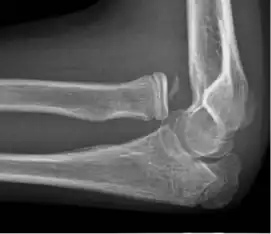

Normal radiograph; right picture of the straightened arm shows the carrying angle of the elbow

When the arm is extended, with the palm facing forward or up, the bones of the upper arm (humerus) and forearm (radius and ulna) are not perfectly aligned. The deviation from a straight line occurs in the direction of the thumb, and is referred to as the "carrying angle".[22]

The carrying angle permits the arm to be swung without contacting the hips. Women on average have smaller shoulders and wider hips than men, which tends to produce a larger carrying angle (i.e., larger deviation from a straight line than that in men). There is, however, extensive overlap in the carrying angle between individual men and women, and a sex-bias has not been consistently observed in scientific studies.[23]

The angle is greater in the dominant limb than the non-dominant limb of both sexes,[24] suggesting that natural forces acting on the elbow modify the carrying angle. Developmental,[25] aging and possibly racial influences add further to the variability of this parameter.